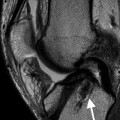

Rehabilitation after anterior cruciate ligament (ACL) reconstruction has evolved over the past 20 years and continues to advance rapidly. The evolution in rehabilitation after ACL reconstruction is in part a result of the development of different surgical procedures that address ACL injuries. In particular, recent efforts to anatomically reconstruct the ACL, which is defined as the functional restoration of the ACL to its native dimensions, collagen orientation, and insertion sites1 is an important consideration for postoperative rehabilitation. Anatomic ACL reconstruction may result in a more rapid return of range of motion (ROM); however, the in situ forces in an anatomically placed graft are greater (comparable with the native ACL) than those in a nonanatomically placed graft (less force than the native ACL as a result of nonanatomic position of the graft).2 As a result, rehabilitation and return to sport after anatomic ACL reconstruction may need to be progressed slower than after traditional, nonanatomic ACL reconstruction.